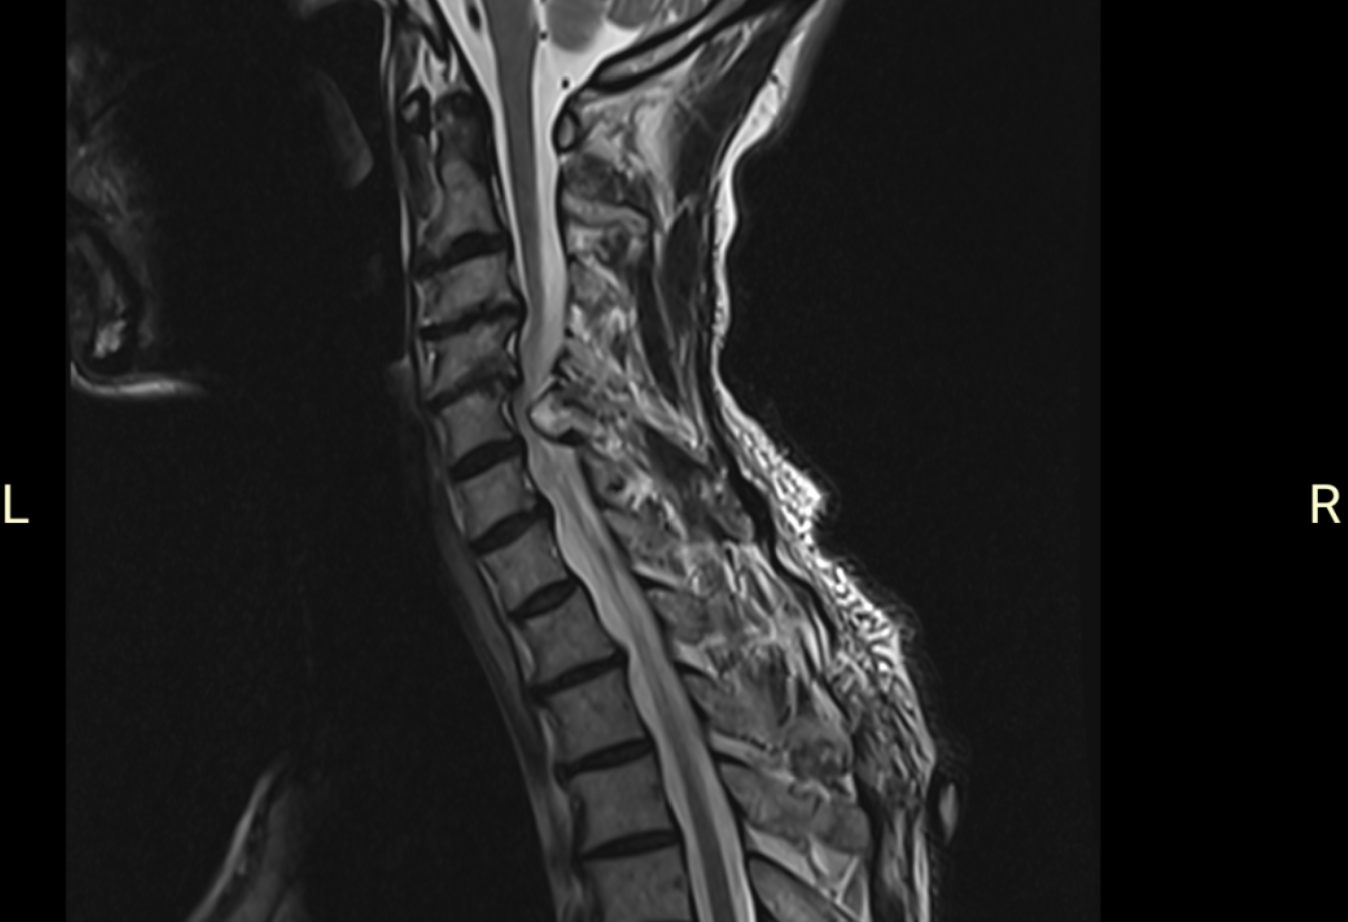

为明确诊断,立即为患者安排颈椎磁共振(MRI)检查。

影像结果清晰显示:颈椎多节段椎间盘突出,相应节段椎管狭窄,颈髓明显受压变形。医生初步考虑是脊髓型颈椎病,需要手术治疗。